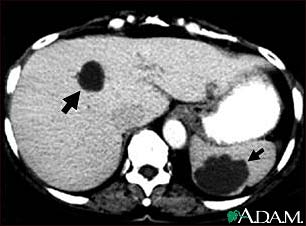

This abdominal CT scan shows multiple cysts in the liver and spleen. Note the dark circular cyst in the liver (left side of screen) and the large, irregular, circular cyst in the spleen (bottom, right side of screen).